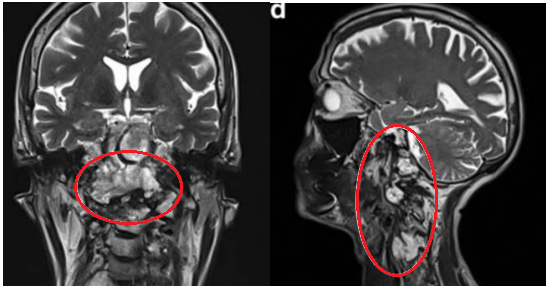

▼图e:术后用骨水泥填充术腔,从中斜坡至C2椎体水平。术后10天行枕-颈固定术。

▼图f:术后MRI显示肿瘤完全切除,患者首次术后10天接受枕颈固定,无并发症。

术后接受质子治疗,术后9个月随访未见影像学复发征象。临床检查无神经功能缺损,患者恢复日常活动。